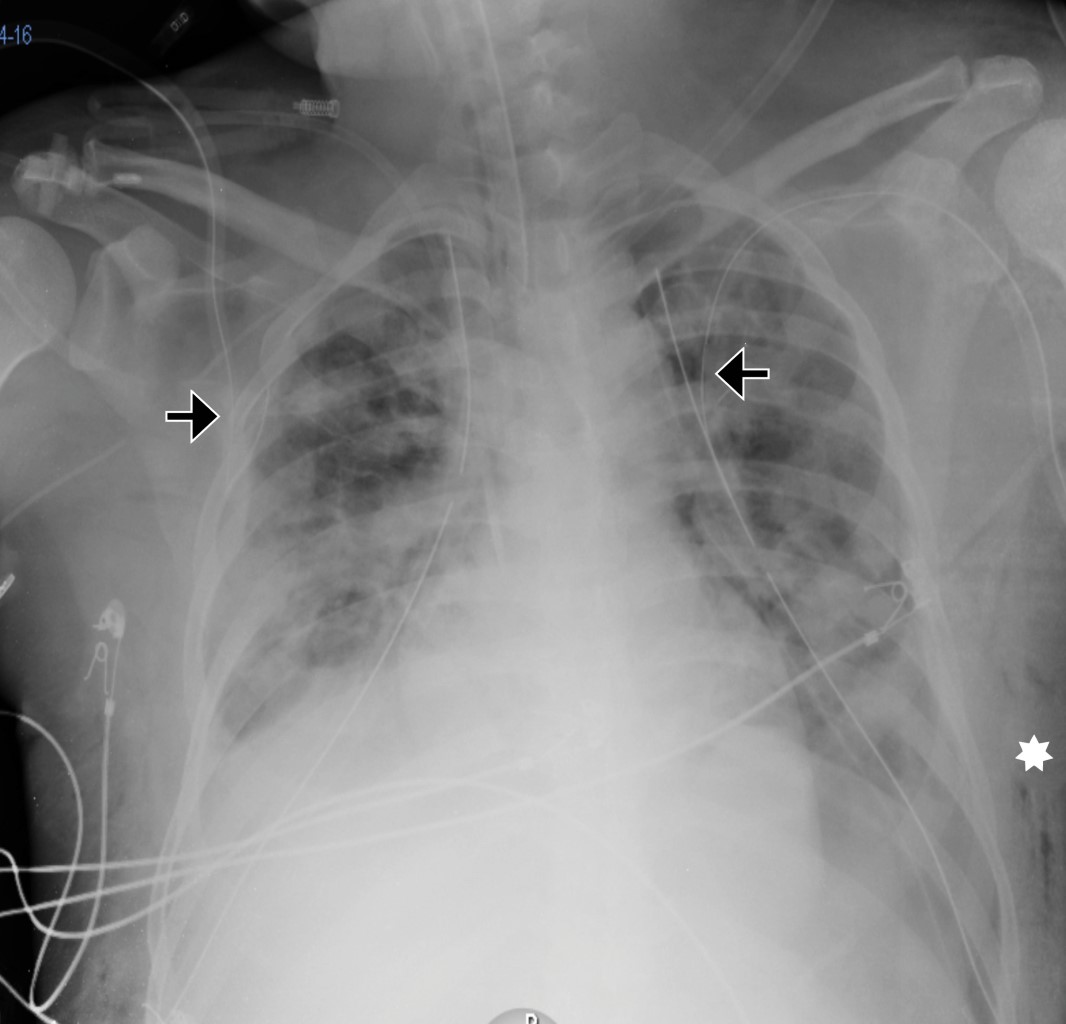

Extensive subcutaneous emphysema

Subcutaneous emphysema is common complication self-limited complication of tube thoracostomy. Any subcutaneous emphysema on positive pressure ventilation, causing palpable cutaneous tension, palpebral closure, dysphagia, and dysphonia or associated with pneumoperitoneum, airway compromise, "tension phenomenon" and respiratory failure is labelled extensive subcutaneous emphysema.

Figure 1